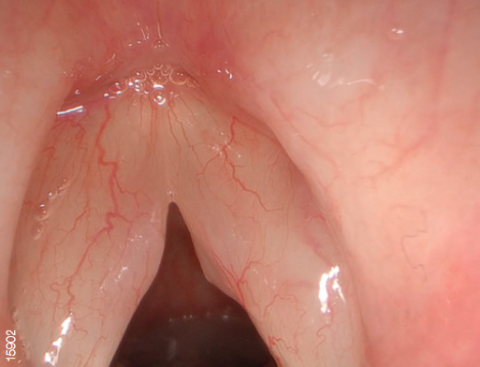

Видеосистема поддерживает режим узкоспектральной визуализации NBI.

NBI - это оптическая технология, которая позволяет визуализировать мельчайшие структуры кровеносных сосудов и слизистой оболочки. В основе технологии лежит принцип поглощения гемоглобином волн определенного спектра (415 и 540 нм). Благодаря уникальным правилам распределения цветов, конечное изображение имеет цветопередачу отличную от обычной.

Свет, попадая в биологическую ткань рассеивается, часть волн (синих и зеленых) поглощается гемоглобином, остальное же распределяется в другие ткани. Поэтому цвет слизистой оболочки желудочно-кишечного тракта в основном определяется гемоглобином. Как упоминалось выше, NBI использует узкополосное освещение с центральной длиной волны 415 и 540 нм. Эти длины волн соответствуют двум пикам поглощения гемоглобина.

Данная технология позволяет с большей точностью визуализировать кровеносные сосуды и слизистую оболочку, а также диагностировать патологические процессы.